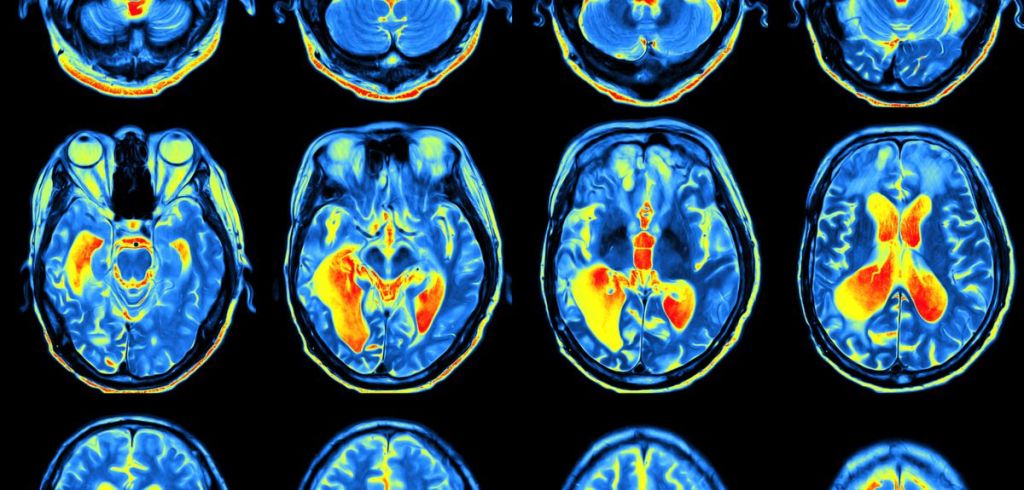

The researchers from the Department of Experimental Psychology, the Wellcome Centre for Integrative Neuroimaging (WIN) and the Nuffield Department of Clinical Neurosciences, used an MRI scanner to observe changes in parts of the brain associated with learning and learned experiences while volunteers completed tasks that involved a reward.